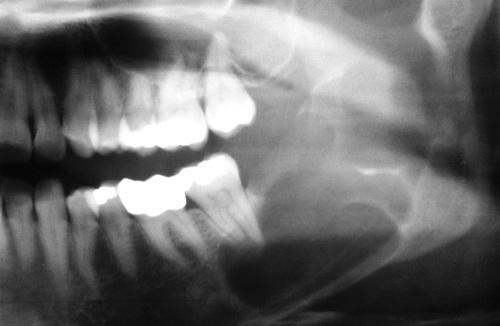

This large, multilocular cyst involves most of the ascending ramus and is growing in an anteroposterior direction.

odontogenic keratocyst (OKC)